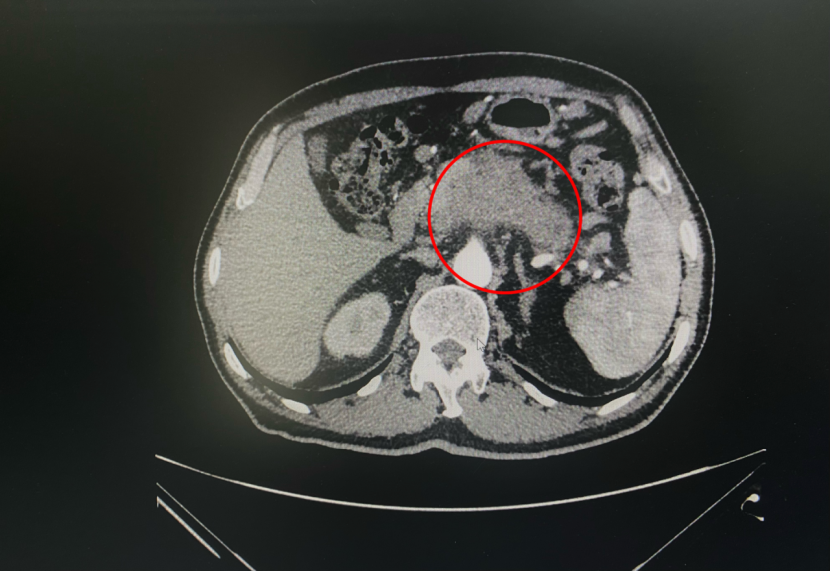

来到南京找到钱祝银主任后,考虑到外地患者就医困难,而且付先生的病情复杂、还有高血压、脑梗、主动脉及冠状动脉粥样硬化、糖尿病、肺气肿、右肾囊肿、膜性肾病等基础疾病,随后专家组立刻为他开启快速就医通道,全程指导入院。针对患者的基础状况和疾病做充分的术前评估,钱祝银主任介绍:付先生的胰腺癌(大小约7.9ⅹ4.3cm),已经侵犯周围血管、胃壁、十二指肠,已经无法手术切除了,而且传统的放化疗效果也不是很好,唯一的办法就是进行冷热复合消融手术治疗。经过我们评估,虽然付先生的病情复杂,但是将基础疾病控制稳定,是可以进行这一项手术治疗的。

肿瘤位置